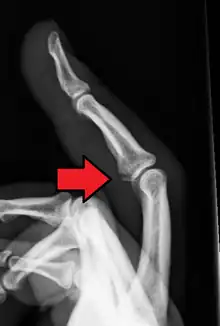

Avulsion fracture of a fingertip bone

Avulsion fracture of the proximal middle phalanx on the palm side